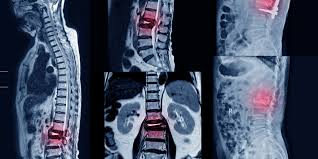

Señales de alerta para descartar fracturas vertebrales en pacientes con dolor lumbar

La evidencia disponible no apoya el uso de muchas señales de alerta para descartar específicamente fracturas vertebrales en pacientes con dolor lumbar (DL). Sobre la base de la evidencia de estudios individuales, pocas señales de alerta individuales parecen informativas debido a que la mayoría tienen una exactitud diagnóstica deficiente según lo indican los cálculos imprecisos de los cocientes de probabilidad. Cuando se usaron combinaciones de señales de alerta el rendimiento pareció mejorar. Cochrane Database Syst Rev. 28 de noviembre de 2023